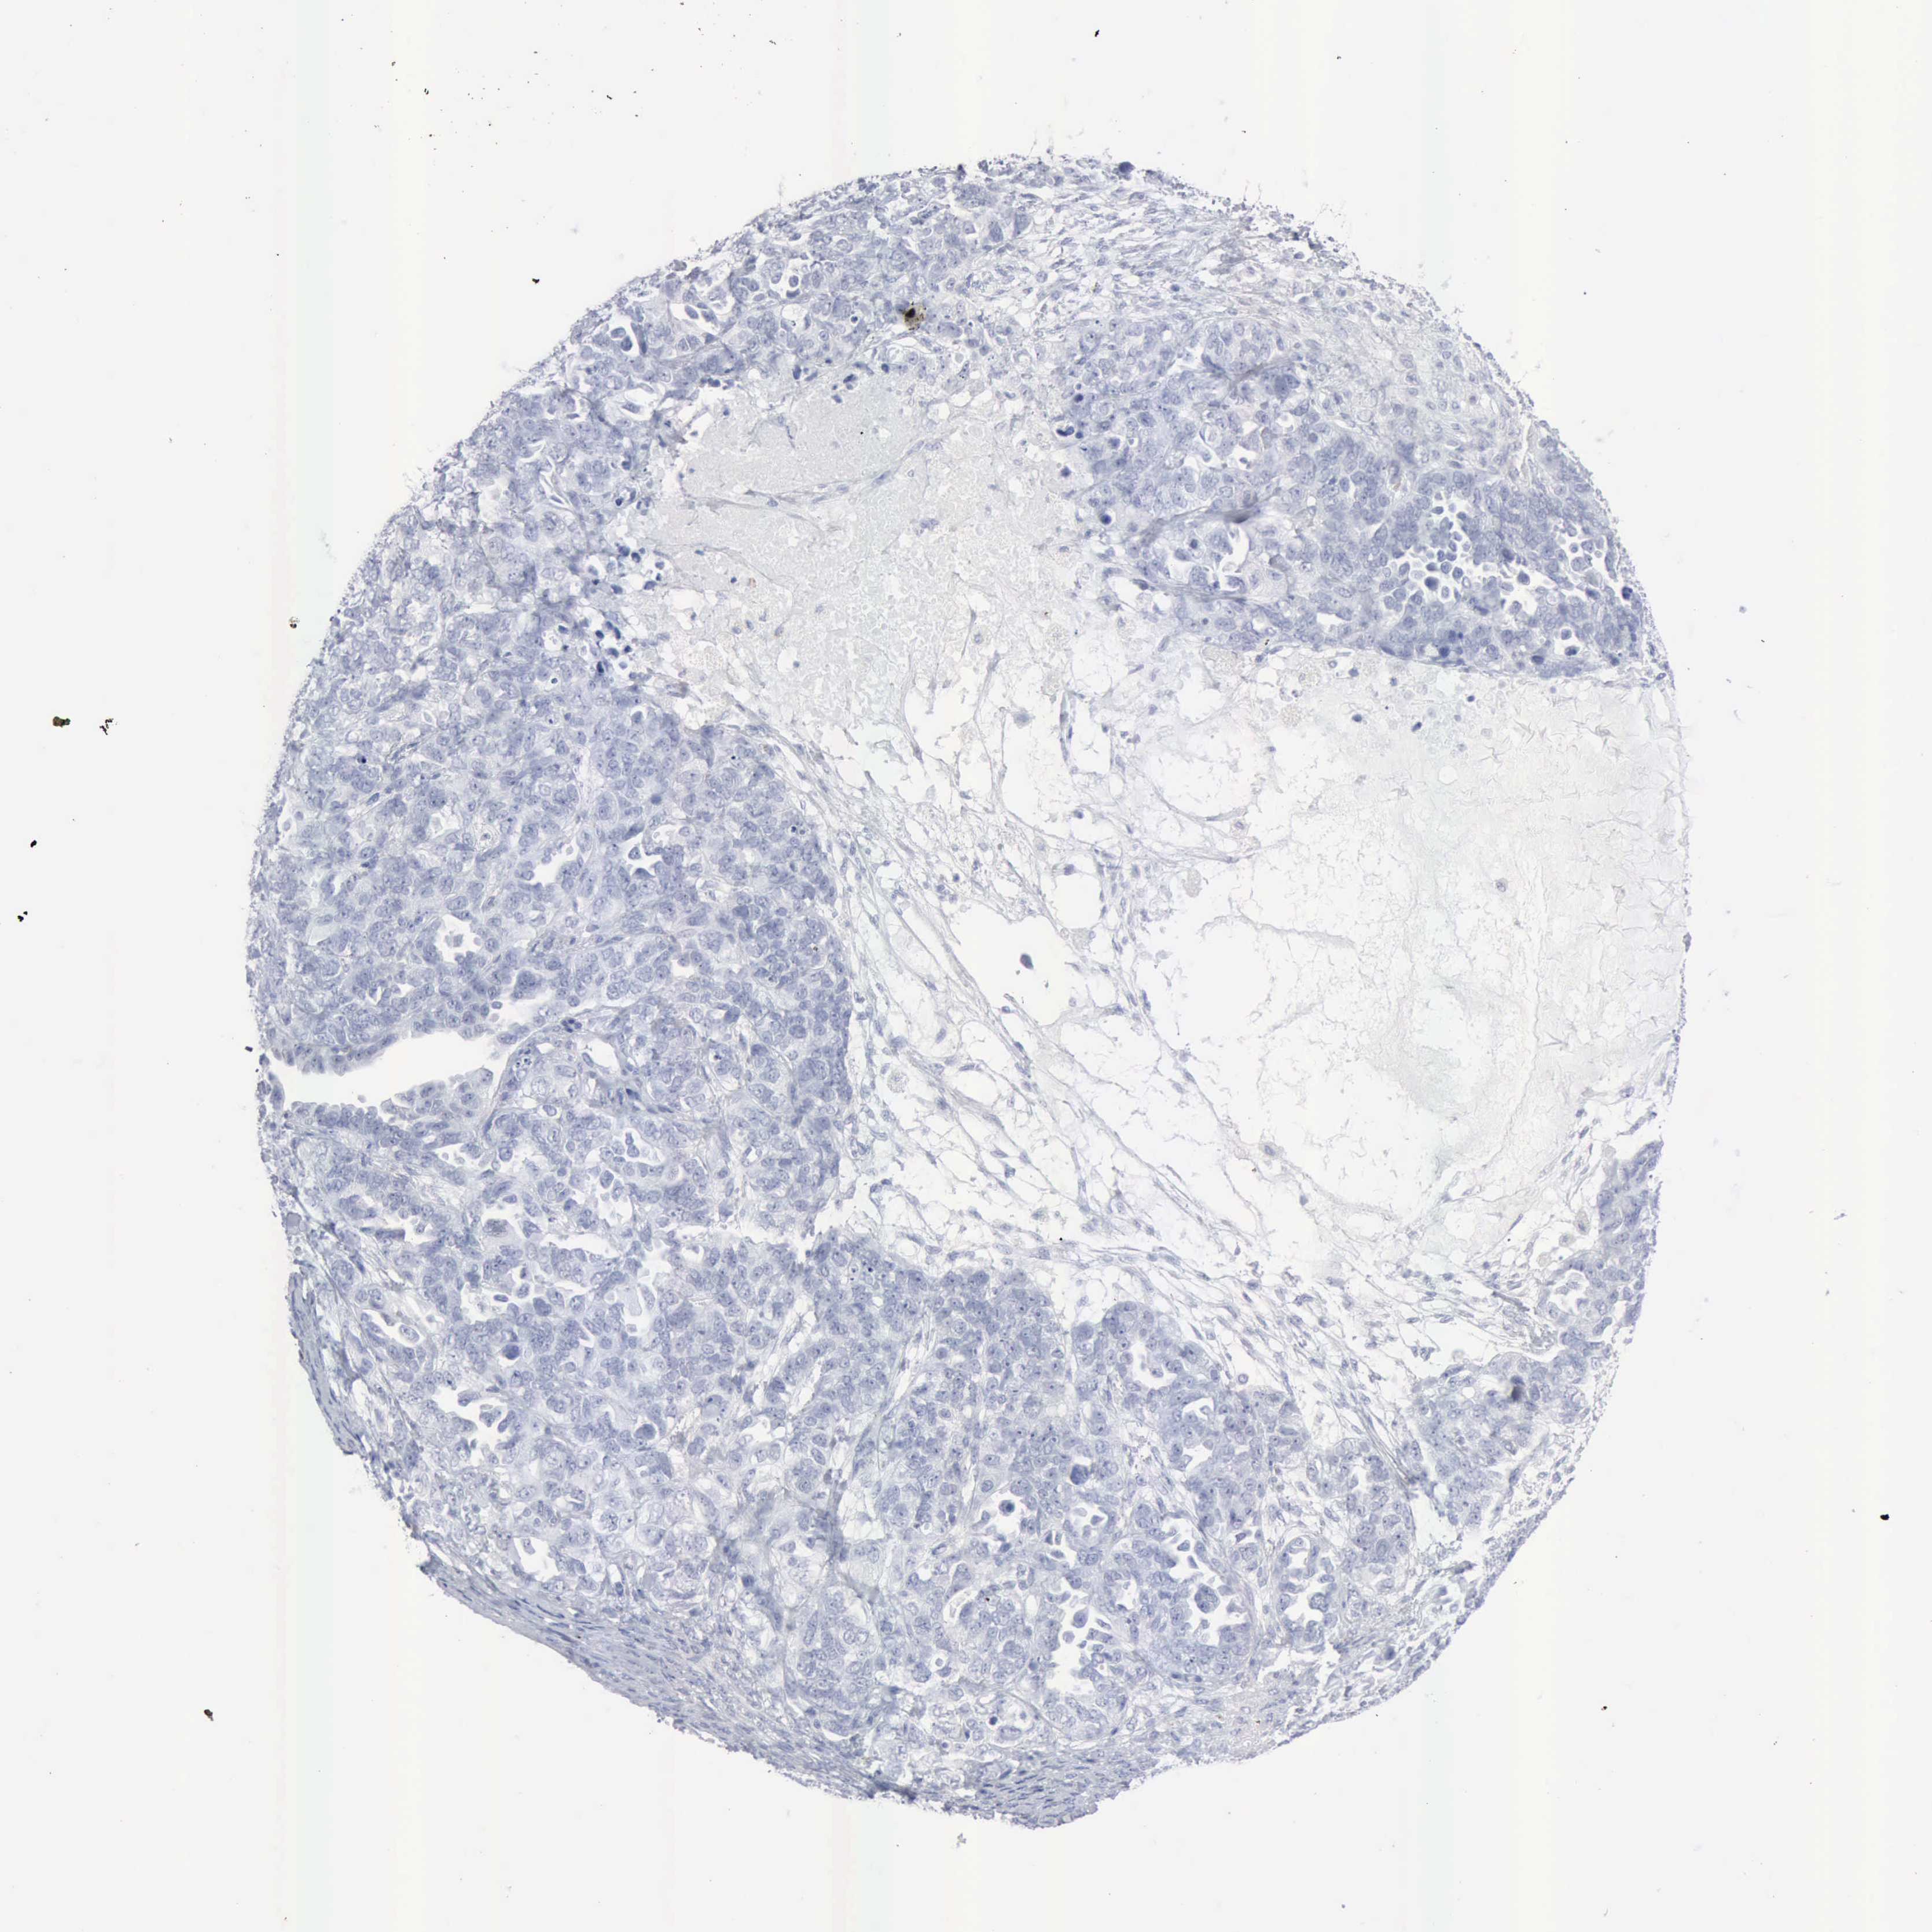

OVARIAN CANCER - Protein expressioni

A mouse-over function shows sample information and annotation data. Click on an image to view it in a full screen mode. Samples can be filtered based on level of antibody staining by selecting one or several of the following categories: high, medium, low and not detected. The assay and annotation is described here.

Note that samples used for immunohistochemistry by the Human Protein Atlas do not correspond to samples in the TCGA dataset.

Antibody stainingi

Antibody staining in the annotated cell types in the current human tissue is reported as not detected, low, medium, or high, based on conventional immunohistochemistry profiling in selected tissues. This score is based on the combination of the staining intensity and fraction of stained cells.

Each image is clickable and will lead to virtual microscopy that enables deeper exploration of all samples and also displays staining intensity scores, fraction scores and subcellular localization as well as patient and tissue information for each sample.

Antibody HPA000237

Antibody HPA000966

Cystadenocarcinoma, mucinous, NOS

Carcinoma, endometroid

Cystadenocarcinoma, serous, NOS